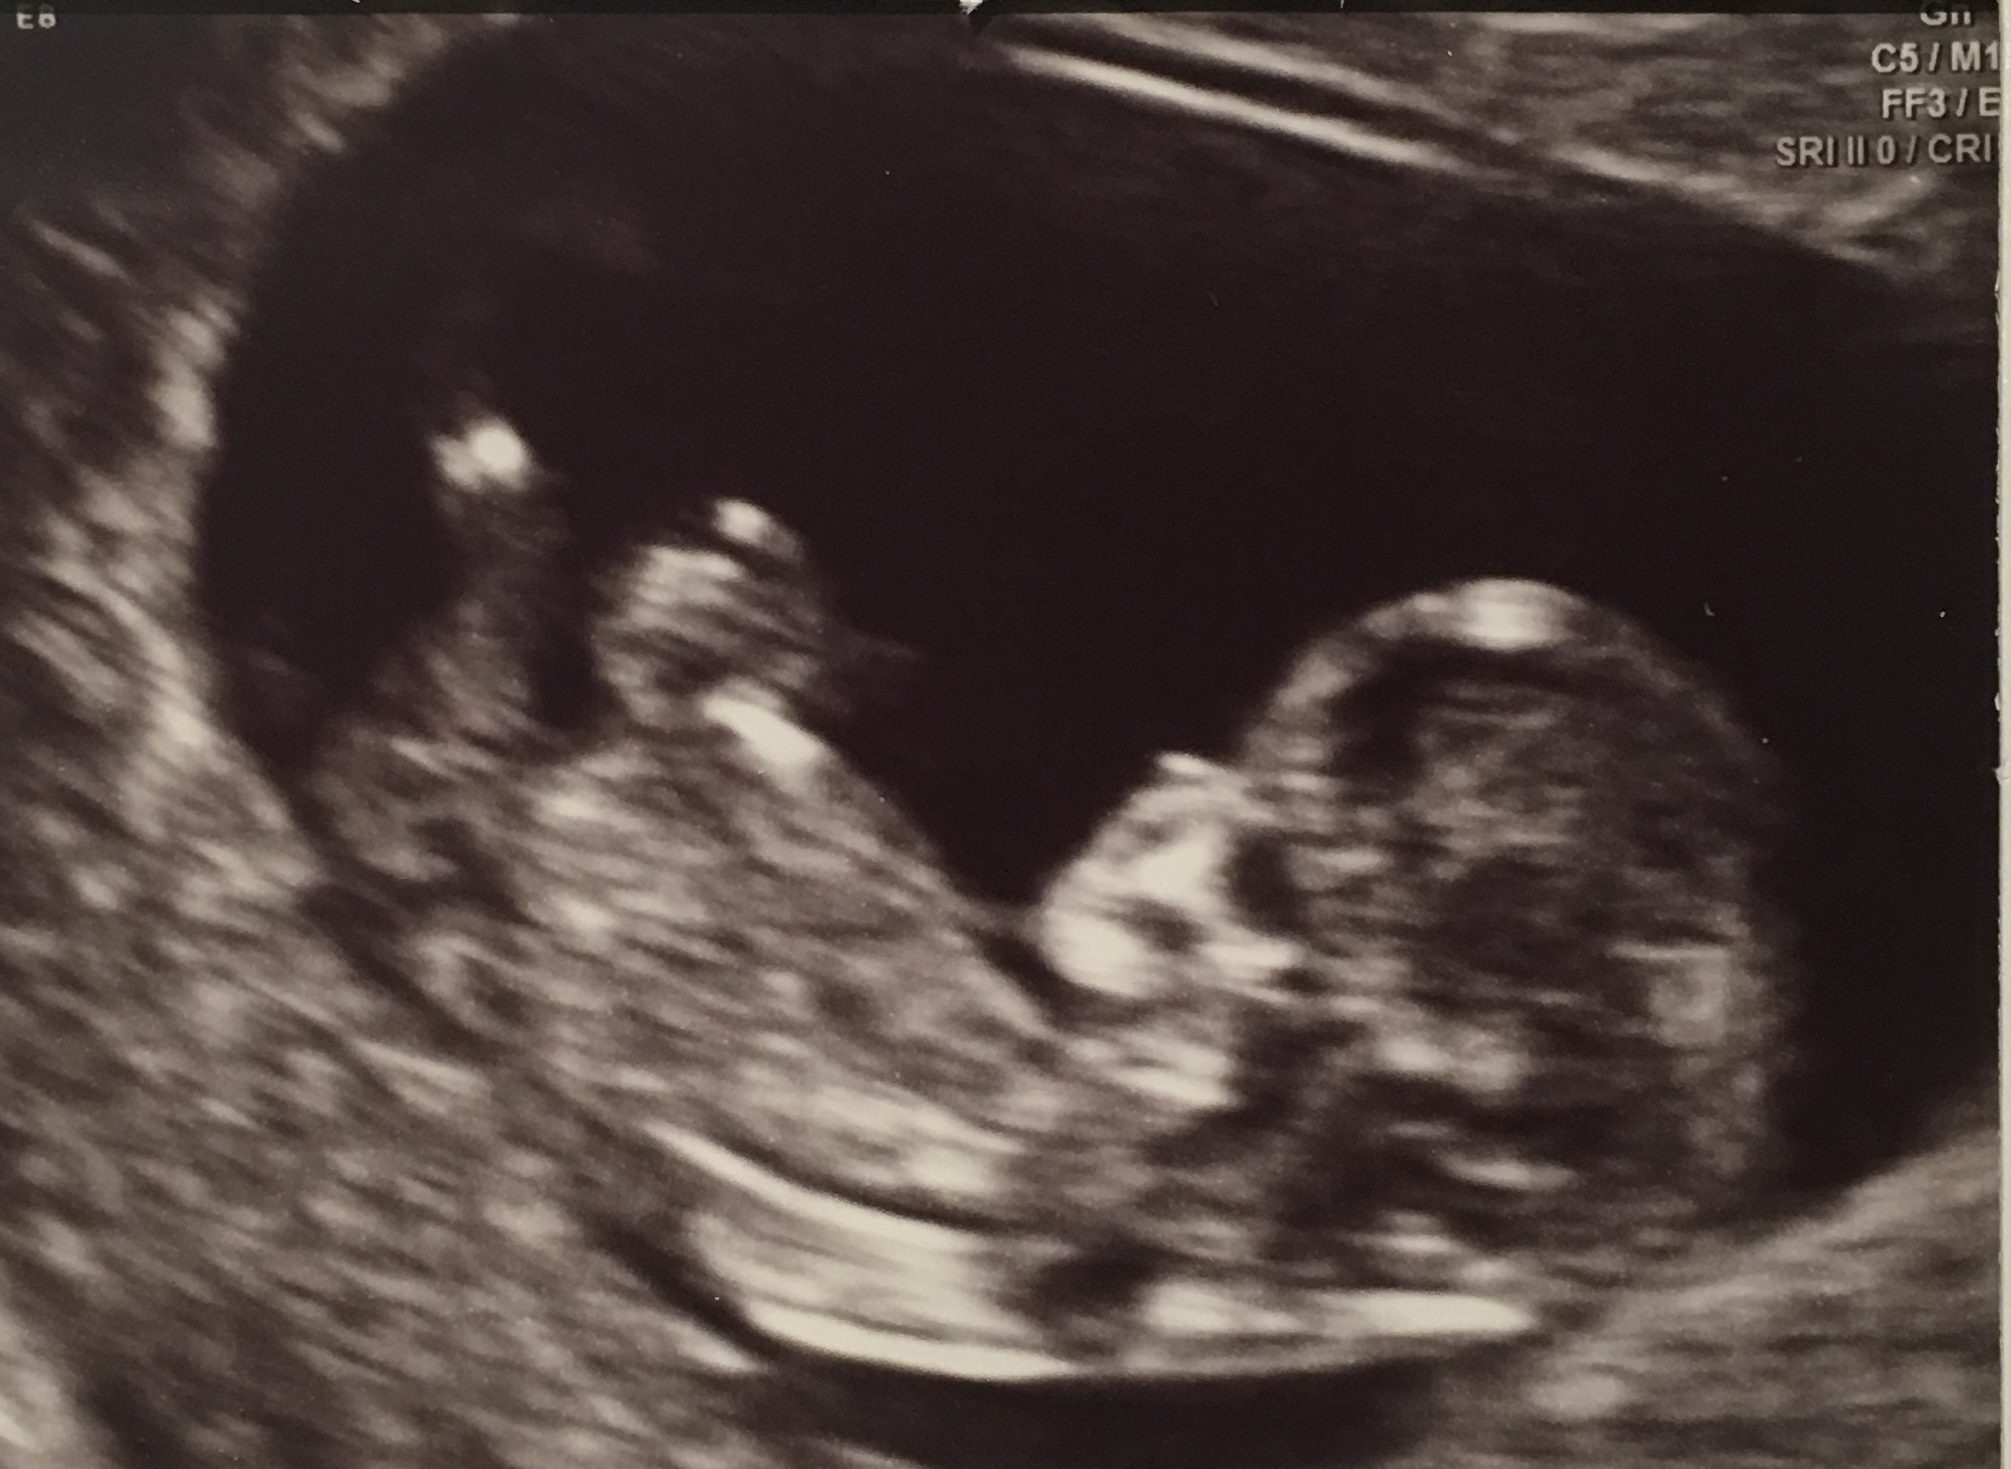

• Forty weeks of feasting

← Poppyseed to Pumpkin; the sequel